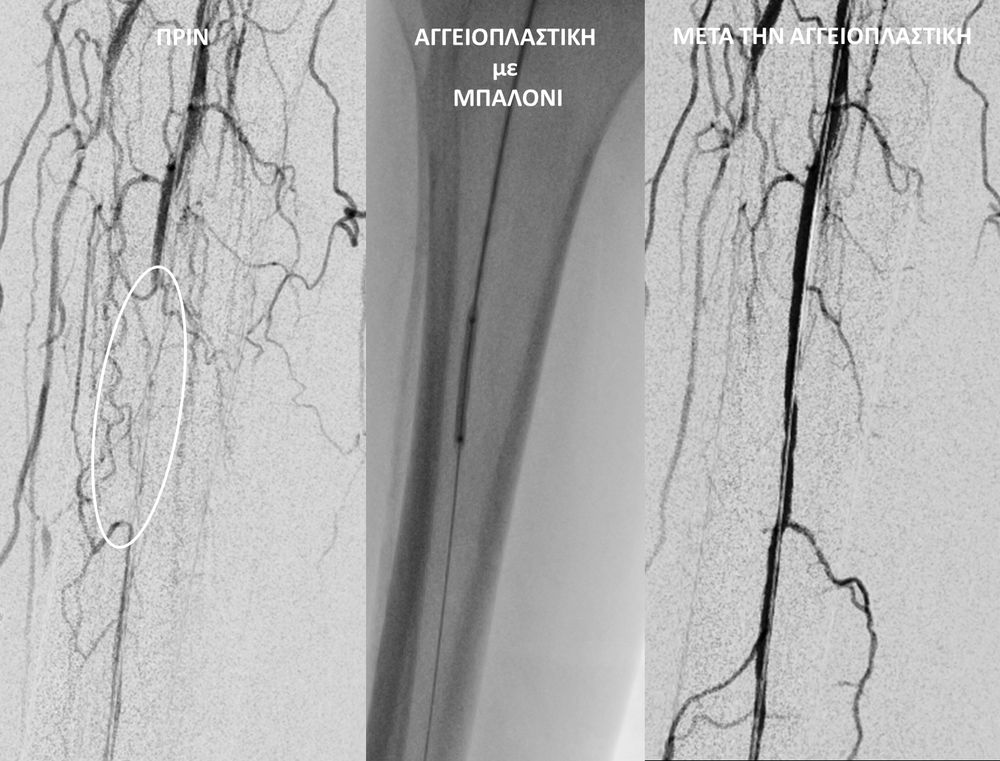

O σακχαρώδης διαβήτης είναι μεταβολική ασθένεια η οποία χαρακτηρίζεται από αύξηση της συγκέντρωσης του σακχάρου στο αίμα (υπεργλυκαιμία) και διαταραχή του μεταβολισμού της γλυκόζης. Ο βαθμός αύξησης της γλυκόζης στο αίμα και η παραμονή των αυξημένων τιμών της για μεγάλο χρονικό διάστημα βλάπτουν, κυρίως, τα μικρά αγγεία, προκαλώντας διαβητική νευροπάθεια, διαβητική νεφροπάθεια, αμφιβληστροειδοπάθεια κ.τ.λ., με σοβαρότατες συνέπειες σε πολλά όργανα-συστήματα.Στην Ελλάδα κάθε χρόνο πραγματοποιούνται 2.000 – 3.000 ακρωτηριασμοί κάτω άκρων, αφού το 4-5% των πασχόντων από διαβήτη εμφανίζει περιφερική αγγειοπάθεια με έλκη ή και γάγγραινα στα πόδια. Σε ποσοστό 80% οι ακρωτηριασμοί θα μπορούσαν να αποφευχθούν και η επεμβατική ακτινολογία μπορεί να βοηθήσει σημαντικά.Η διαδερμική ενδαγγειακή αγγειοπλαστική (percutaneous transluminal angioplasty, PTA) είναι μια ελάχιστα επεμβατική μέθοδος αντιμετώπισης των αρτηριακών στενώσεων ή και αποφράξεων του διαβητικού ποδιού (περιφερικήδιαβητικήαρτηριοπάθεια).